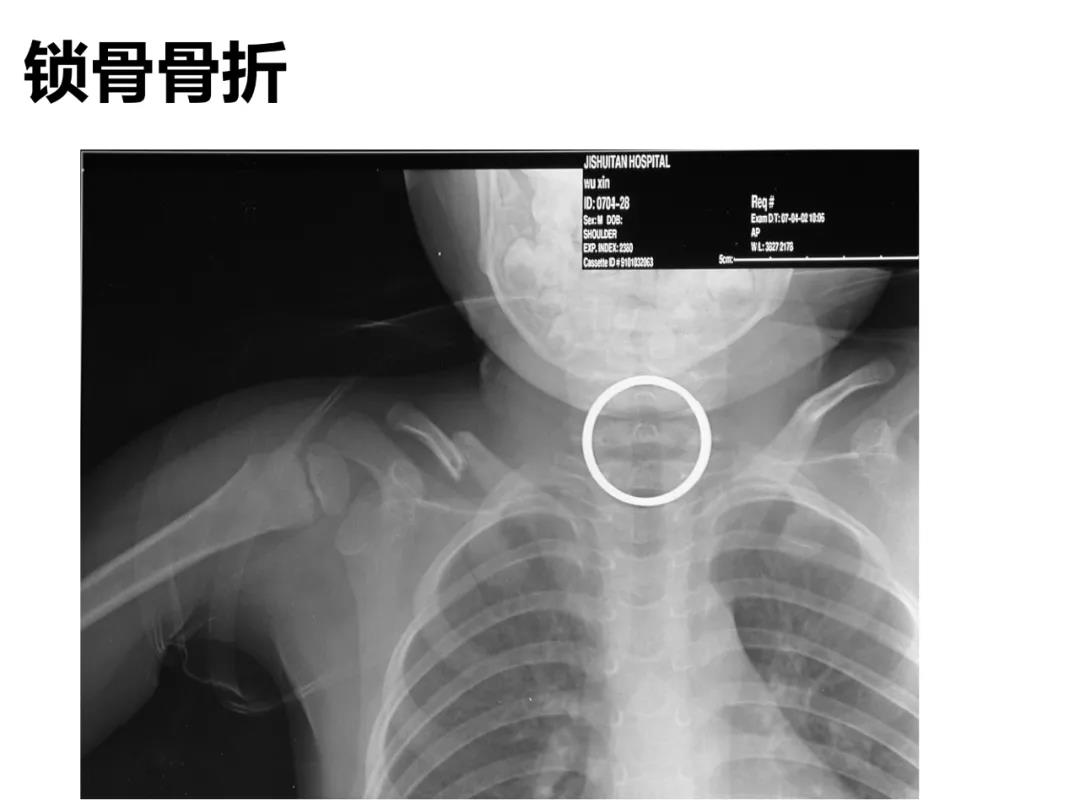

小儿骨科X线片汇总,临床读片宝典!